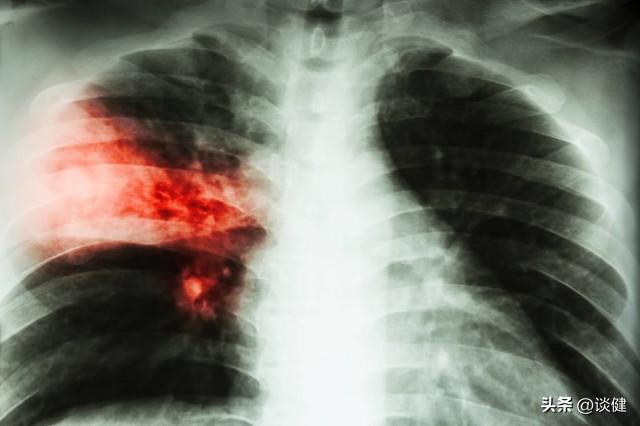

临床上也有数起因电子烟造成肺伤害的案例,其中不乏青少年族群。曾一位15岁少年出现呼吸喘、咳嗽、上腹痛、呕吐等症状,经胸部X线及胸部CT检查发现双侧肺炎,排除感染及其他原因后,经过询问,少年坦承11岁起开始抽电子烟,烟龄4年,确认是由电子烟造成的肺部损伤。